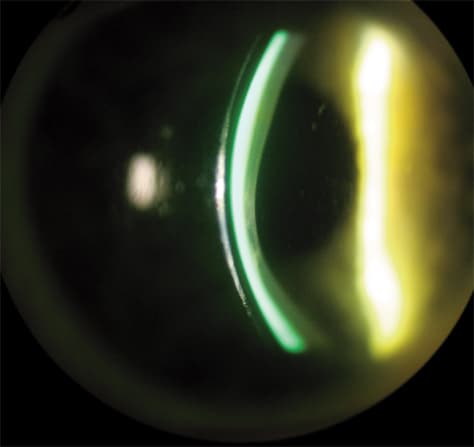

Scleral RGP contact lenses (Figure 3), which are defined as having a diameter of 18 mm to 24 mm, are making a comeback into mainstream specialty-lens fitting. Their inherent advantage to fitting irregular corneas is that they rest on the sclera and vault the corneal surface. This provides the patient with comfortable wear and stable vision. They trap a tear reservoir (Figure 4) that not only masks corneal irregularity, but also can act as a bandage for the anterior surface. The best way to begin fitting these lenses is to call an RGP laboratory that makes them, such as Medlens Innovations or Essilor of America Inc. (Dallas) and purchase a trial lens set, using their fitting guide for reference. When you first start using these lenses, consultation with the lab will be critical to your success during the learning curve.

Figure 4. Scleral RGP contact lenses also trap a tear reservoir that masks corneal irregularity and acts as a bandage for the anterior surface.